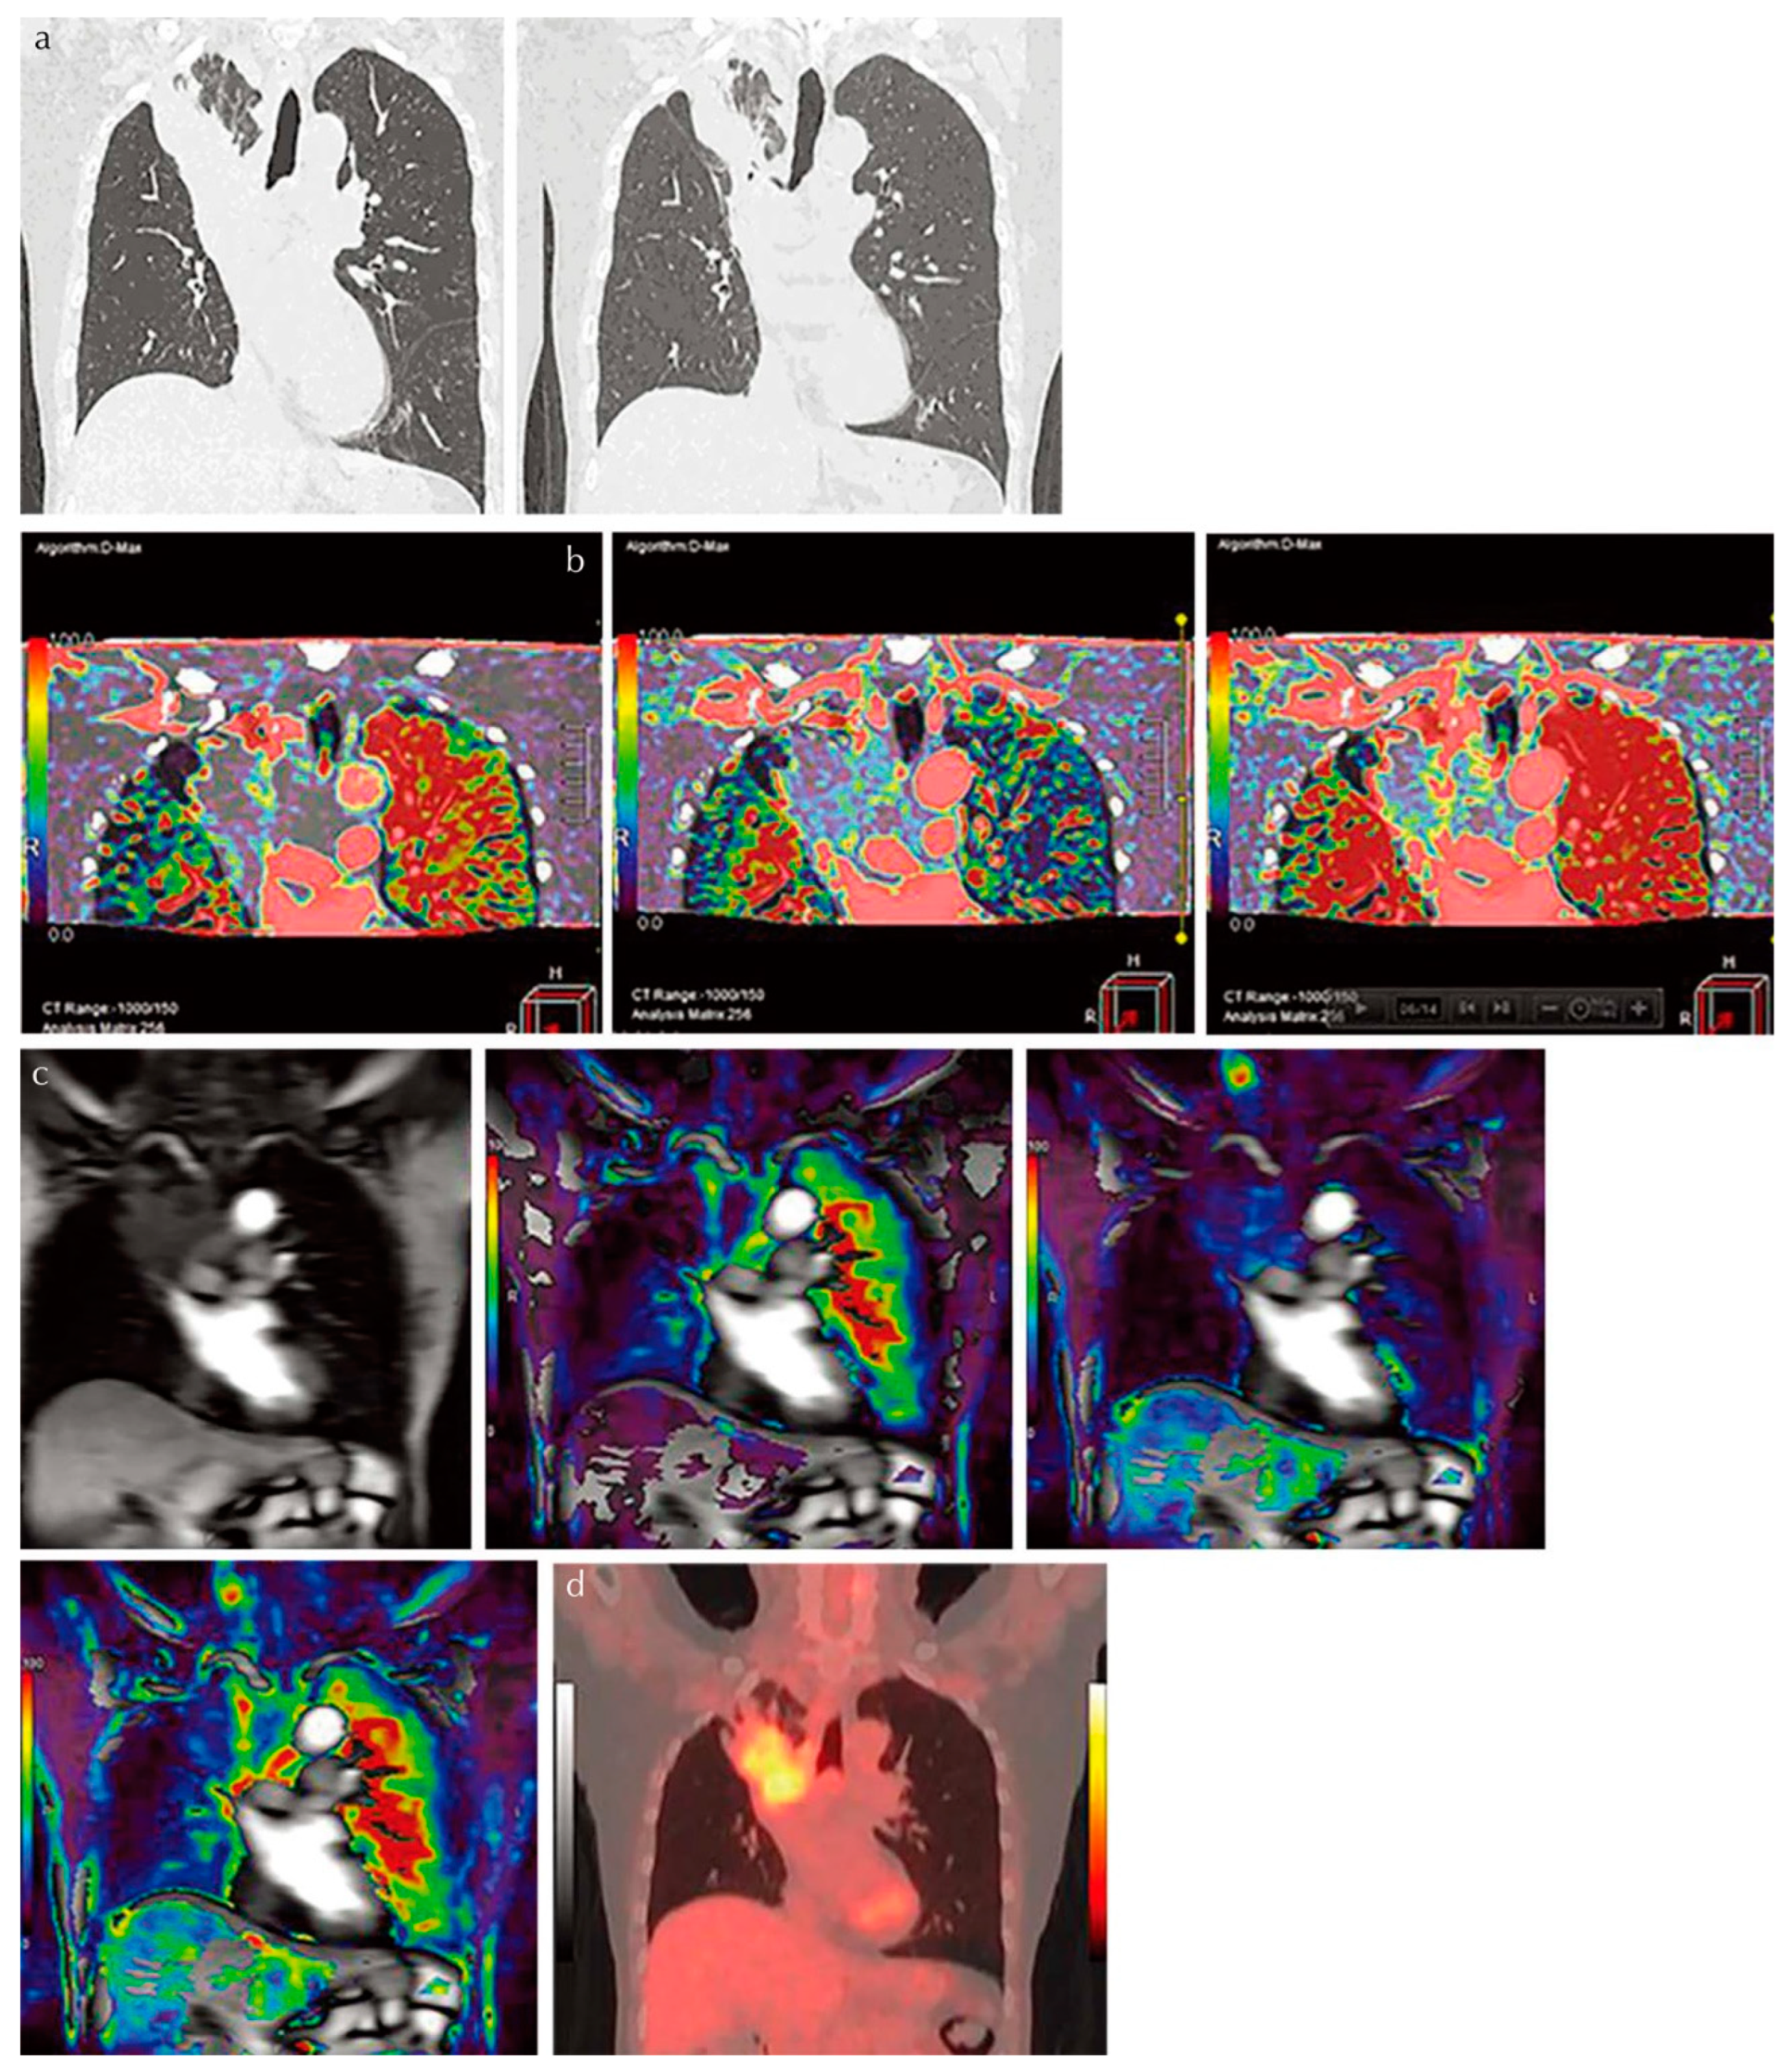

- Ohno, Y.; Koyama, H.; Fujisawa, Y.; Yoshikawa, T.; Seki, S.; Sugihara, N.; Sugimura, K. Dynamic contrast-enhanced perfusion area detector CT for non-small cell lung cancer patients: Influence of mathematical models on early prediction capabilities for treatment response and recurrence after chemoradiotherapy. Eur. J. Radiol. 2016, 85, 176–186. [Google Scholar] [CrossRef] [PubMed] [Green Version]

- Ohno, Y.; Koyama, H.; Lee, H.Y.; Miura, S.; Yoshikawa, T.; Sugimura, K. Contrast-enhanced CT- and MRI-based perfusion assessment for pulmonary diseases: Basics and clinical applications. Diagn. Interv. Radiol. 2016, 22, 407–421. [Google Scholar] [CrossRef] [Green Version]

- Ohno, Y.; Fujisawa, Y.; Koyama, H.; Kishida, Y.; Seki, S.; Sugihara, N.; Yoshikawa, T. Dynamic contrast-enhanced perfusion area-detector CT assessed with various mathematical models: Its capability for therapeutic outcome prediction for non-small cell lung cancer patients with chemoradiotherapy as compared with that of FDG-PET/CT. Eur. J. Radiol. 2017, 86, 83–91. [Google Scholar] [CrossRef] [PubMed] [Green Version]

- Ohno, Y.; Fujisawa, Y.; Sugihara, N.; Kishida, Y.; Seki, S.; Koyama, H.; Yoshikawa, T. Dynamic Contrast-Enhanced Perfusion Area-Detector CT: Preliminary Comparison of Diagnostic Performance for N Stage Assessment With FDG PET/CT in Non–Small Cell Lung Cancer. AJR Am. J. Roentgenol. 2017, 209, W253–W262. [Google Scholar] [CrossRef]

- Ohno, Y.; Fujisawa, Y.; Yui, M.; Takenaka, D.; Koyama, H.; Sugihara, N.; Yoshikawa, T. Solitary pulmonary nodule: Comparison of quantitative capability for differentiation and management among dynamic CE-perfusion MRI at 3 T system, dynamic CE-perfusion ADCT and FDG-PET/CT. Eur. J. Radiol. 2019, 115, 22–30. [Google Scholar] [CrossRef]

- Seki, S.; Fujisawa, Y.; Yui, M.; Kishida, Y.; Koyama, H.; Ohyu, S.; Sugihara, N.; Yoshikawa, T.; Ohno, Y. Dynamic Contrast-enhanced Area-detector CT vs Dynamic Contrast-enhanced Perfusion MRI vs FDG-PET/CT: Comparison of Utility for Quantitative Therapeutic Outcome Prediction for NSCLC Patients Undergoing Chemoradiotherapy. Magn. Reson. Med. Sci. 2020, 19, 29–39. [Google Scholar] [CrossRef] [Green Version]